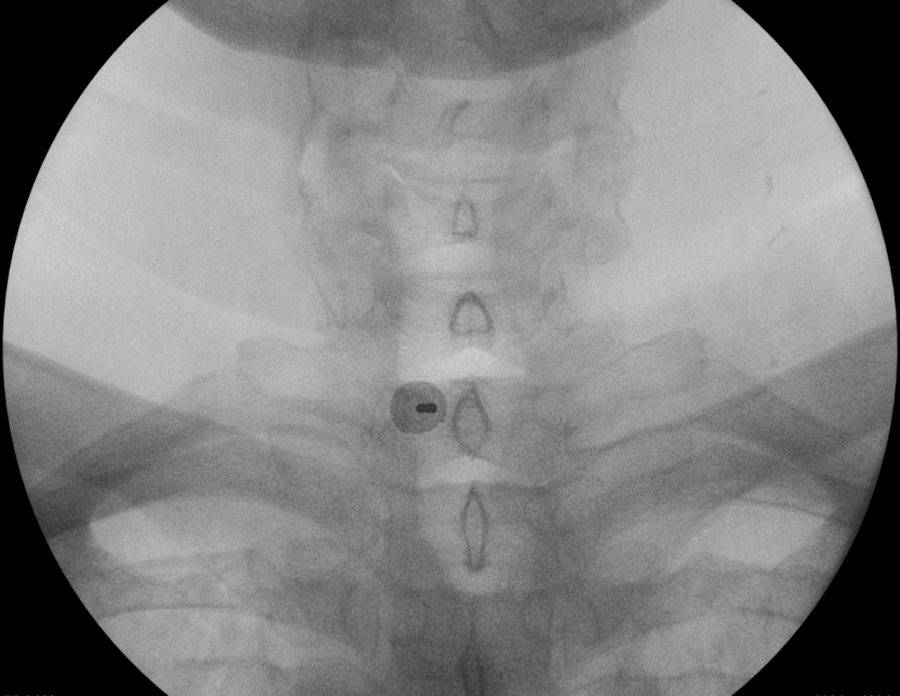

Se comienza con proyecciones A/P para ubicar reparos anatómicos correspondientes. Se decide ingresar por vía interlaminar izquierda, se utilizan proyecciones oblicuas contralateral según normas intervencionistas vigentes al día de la fecha. Se administra contraste no iónico de baja osmolaridad, una vez que se descarta absorción vascular y aspiración negativa de LCR se procede a la administración de anestésico local y corticoide no particulado (dexametasona 8mg).